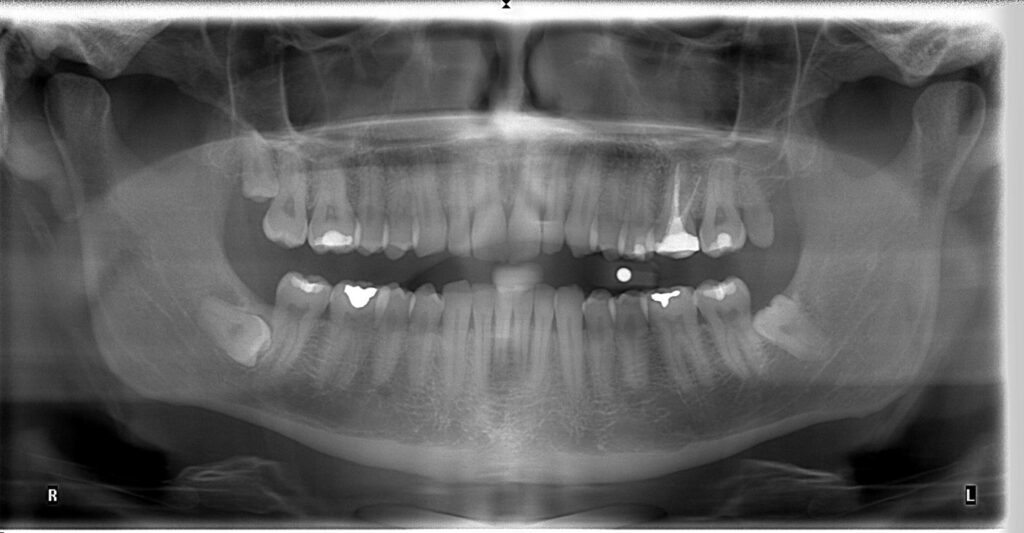

スコーネの住民を対象に最近行われた研究では、症例の半分以上(n=442)で下顎管が第3大臼歯の根より下に位置していることが示されました。これは、パノラマレントゲン写真で下顎管の位置に関する十分な情報が得られることが多いことを意味します。外科的抜歯前の根管の切除(7)。

図 2: 下顎管が歯 38 番と 48 番の下にあることを示すパノラマ X 線。

パノラマ画像における特定の放射線信号に基づいて、神経損傷のリスク増加が確認できます (6)。

下顎管が歯根に重なっている場合には、他の放射線学的方法を使用する必要があります(7)。

図 3: 下顎管が歯 38 の根に重なっていることを示すパノラマレントゲン写真。